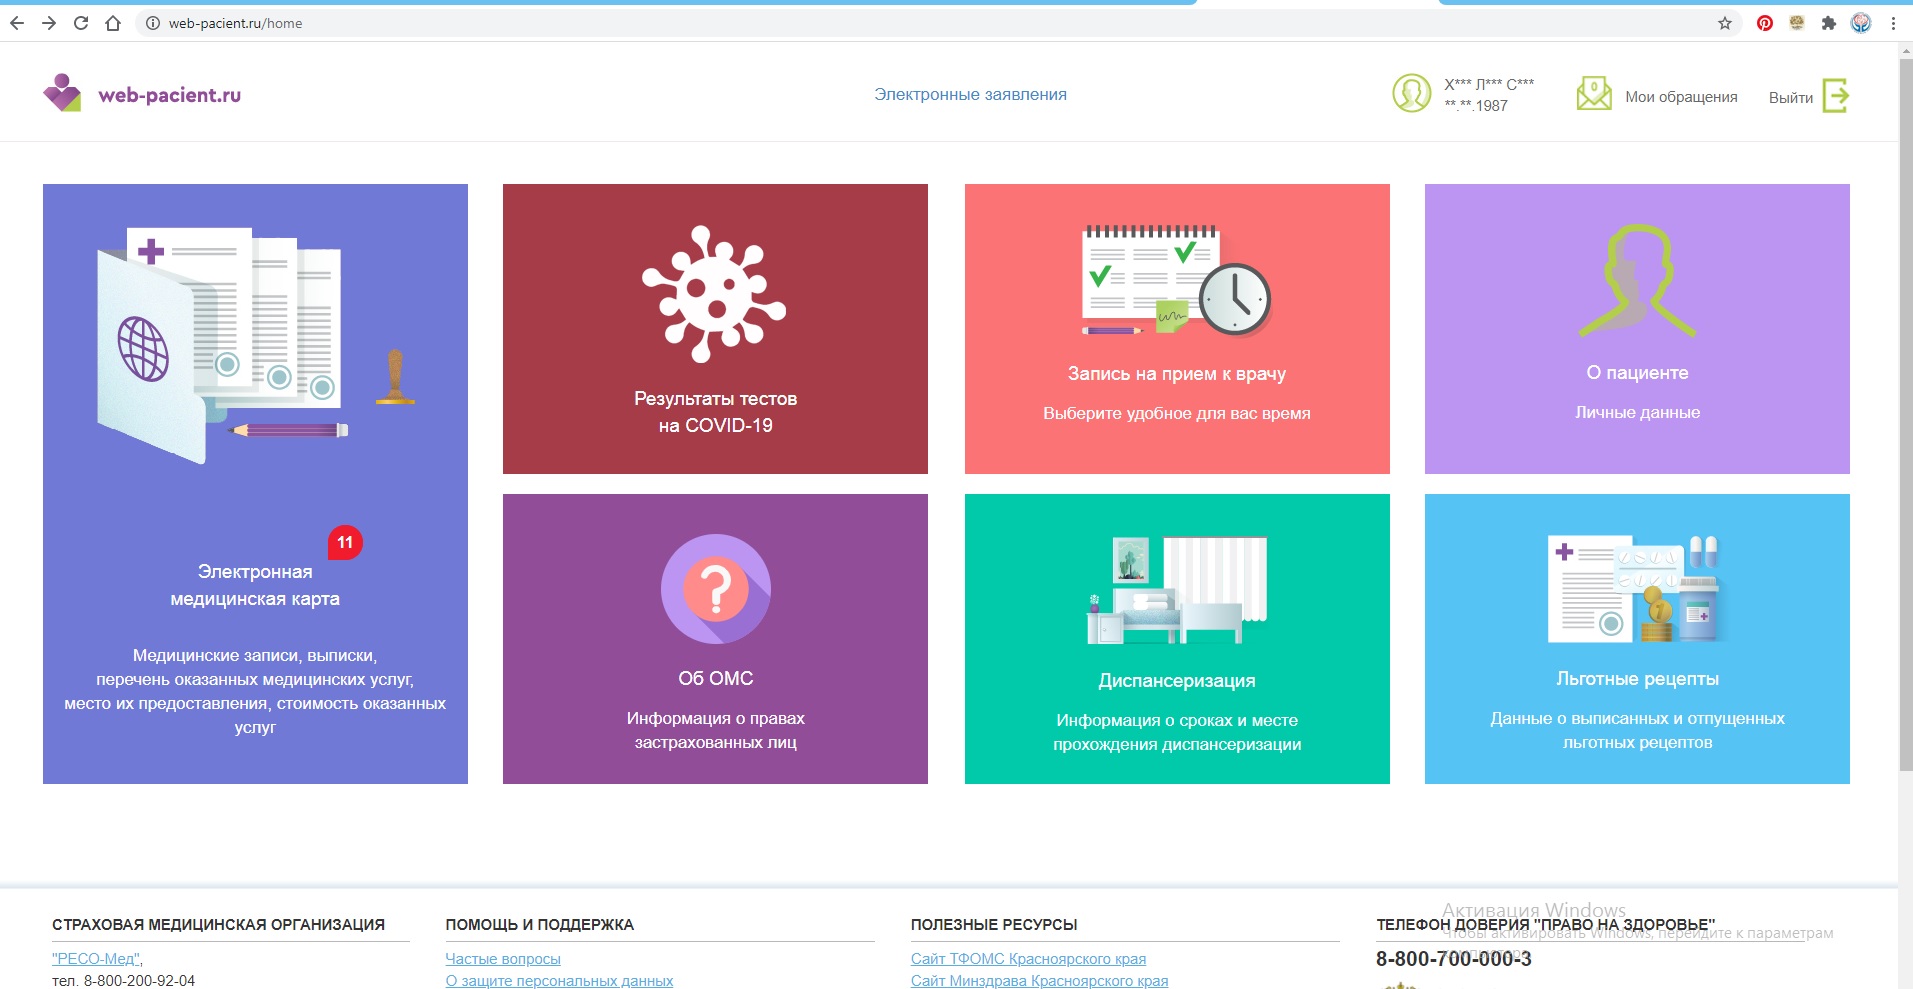

Узнать результат ПЦР-теста на COVID-19 теперь можно в личном кабинете на сайте www.web-pacient.ru

Подробнее...